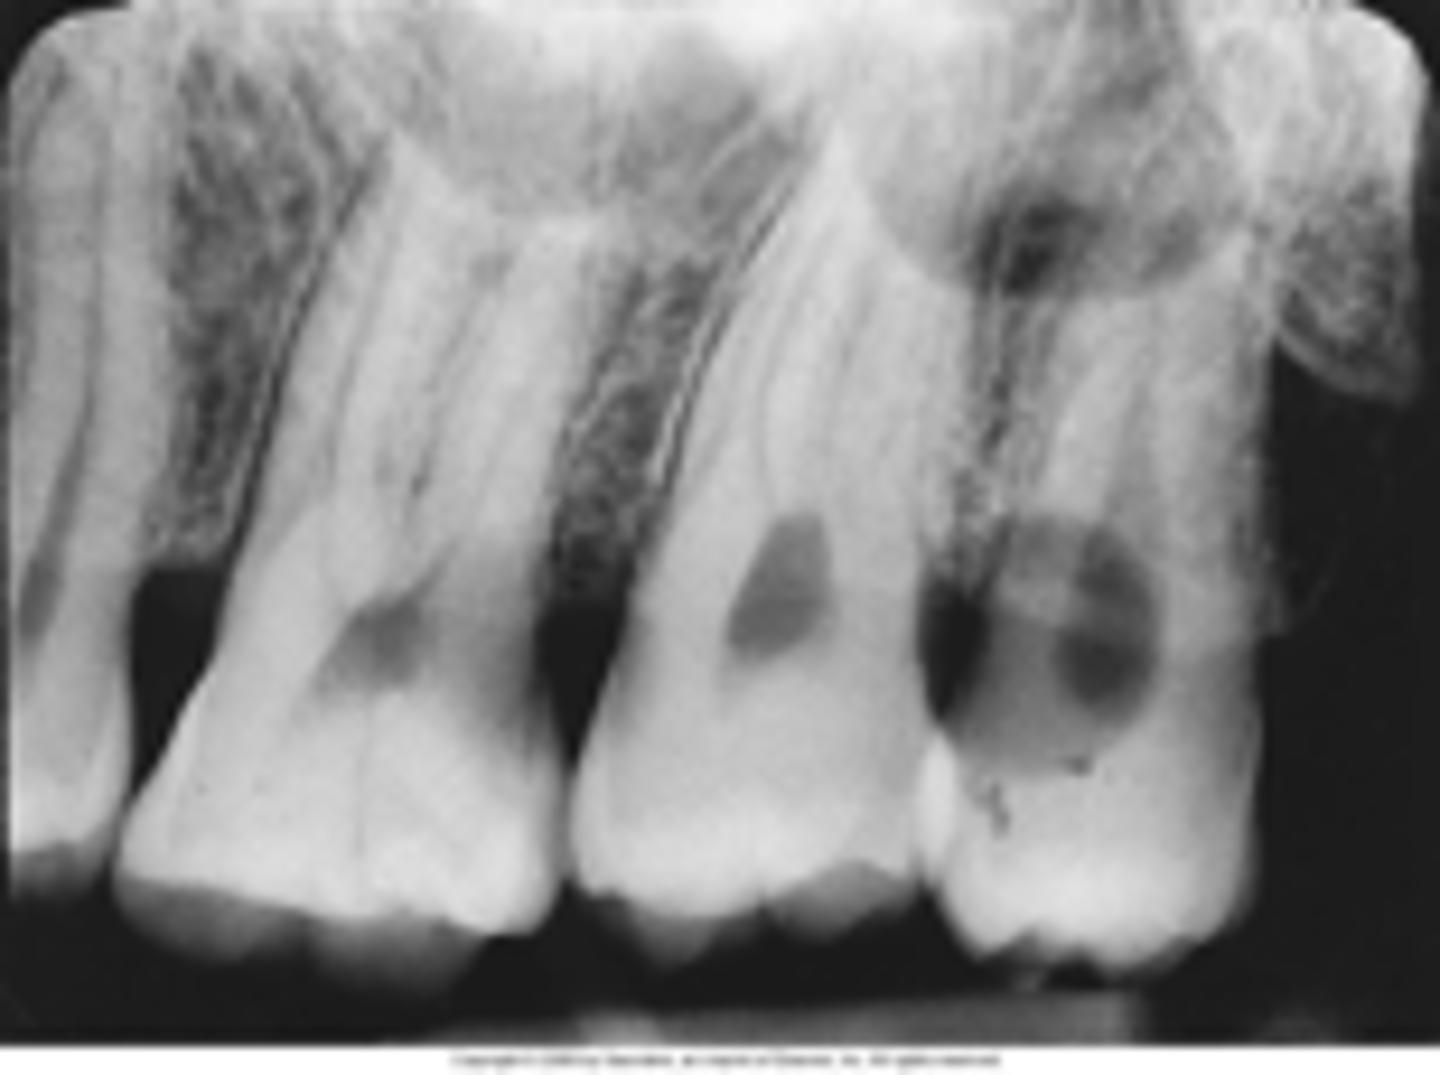

Foreshortened Images

The vertical angulation was excessive, or too steep, and as a result images are shorter than the actual teeth

<p>The vertical angulation was excessive, or too steep, and as a result images are shorter than the actual teeth</p>

Elongated images

Long distorted teeth. Too little vertical angulation.

<p>Long distorted teeth. Too little vertical angulation.</p>